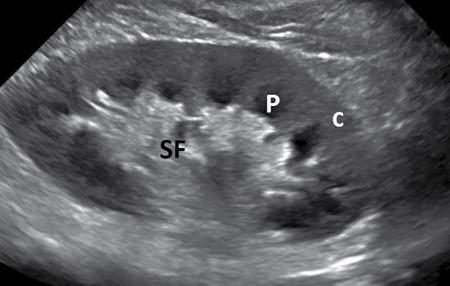

Amit Kumar Kamble, Abhinav Ranwaka The adult urinary system is formed of a pair of kidneys, a pair of ureters, a urinary bladder and a urethra. All these structures are extraperitoneal in location and extend from upper abdomen to the pelvis and into the exterior. These organs can be visualised on a host of imaging modalities, and a knowledge of these appearances helps the radiologist identify the relevant pathologies. Having a complex embryological development, the urinary system can have a wide spectrum of normal and abnormal anatomical variants. This chapter describes the appearance of the urinary system in commonly used imaging modalities and their common variants. Kidneys are paired bean-shaped structures situated in the retroperitoneum on either side of the vertebral column. The kidney consists of The renal sinus contains: The kidneys are surrounded by the renal capsule which is enclosed in the perirenal space. This space predominantly contains the perinephric fat and has thin septations within (Kunin’s septa); these septae may be thickened in various renal pathologies seen as perinephric stranding on imaging. The perirenal space is bounded by the perirenal fasciae, called the Gerota fascia (anterior perirenal fascia) and Zuckerkandl fascia (posterior perirenal fascia). The leaves of perirenal fascia fuse superiorly, laterally and medially. Superiorly, the perirenal fasciae also enclose the adrenal gland, which is separated from the kidney by a septum (Fig. 10.2.2). The anterior and posterior perirenal fasciae fuse laterally to form the lateral conal fascia. Medially, the perirenal fascia also encloses the renal pedicle. Medially, it communicates with renal sinus fat. There may be the communication of perirenal spaces across the midline. Superiorly, the perirenal space communicates with the bare area of the liver or spleen. The ureter arises from the perirenal space and travels inferiorly in anterior pararenal space. Inferiorly, the perinephric space may communicate with periureteric tissues. Interfascial planes are potential planes in between the leaves of the anterior perirenal fascia, called the retromesenteric plane and in the anterior perirenal fascia called the retrorenal plane. Anterior pararenal space: It is bounded by parietal peritoneum anteriorly, anterior perirenal fascia (Gerota) posteriorly and lateral conal fascia laterally. The anterior pararenal space contains the pancreas, second and third part of the duodenum, the retroperitoneal segments of ascending and descending colon and the roots of the small bowel mesentery and transverse mesocolon. Posterior pararenal space: It is bounded by posterior perirenal fascia (Zuckerkandl) anteriorly, fascia transversalis posteriorly and lateral conal fascia laterally. Caudally, the pararenal spaces communicate with each other and also with the extraperitoneal spaces. All the three spaces communicate at the pelvic brim. Understanding of the anatomy of spaces around the kidney is important for local staging of renal pathologies. Renal arteries are the branches of abdominal aorta. They originate laterally from the aorta below the origin of superior mesenteric artery. Accessory unilateral renal artery occurs in 30% of the population and bilaterally in 10% of population. Renal artery is divided into anterior division, which divides into four segmental branches and a posterior division; these arteries are end arteries supplying the respective segments of the kidneys (Fig. 10.2.3): apical, upper, middle, lower segments supplied by the anterior division, and a posterior segment supplied by the posterior division. The segmental arteries divide into lobar branches one to each to renal pyramid. Before reaching to pyramid, they divide into two to three interlobar branches. At the junction of cortex and medulla, interlobar arteries divide into arcuate arteries at the right angle. They further subdivide into interlobular artery, afferent and efferent arterioles. The efferent arteriole drains into peritubular plexus. The plane where the branches of the anterior and posterior divisions meet is located between the anterior two-thirds and posterior one-third of the kidney and is relatively avascular; it is called the avascular plane of Brodel (Fig. 10.2.3), and is a relatively safe site for nephrostomy access. Peritubular plexus converges to form the interlobular vein. These veins accompany their arterial counterparts and drain into the renal vein. The renal veins are situated anteriorly to the renal arteries and finally drain into the inferior vena cava at the right angles (Fig. 10.2.4). The two left renal veins may be present one passing anterior and other posterior to the aorta known as persistence of renal collar. Sometimes a single retroaortic left renal vein (Fig. 10.2.5) may be present. Supernumerary right renal vein may be seen. Renal vein variations are more common on the right side. The lymphatics of the kidneys drain into the lateral aortic nodes at the level of origin of renal arteries. Normal kidneys may be visualised on a frontal abdominal radiograph as faint oval shadows on either side of the vertebral column immediately besides the psoas shadows (Fig. 10.2.6). On contrast radiography and intravenous urography, the renal shadows show gradual opacification, peaking between 30 and 60 seconds followed by opacification of the pelvicalyceal system on subsequent radiographs. The kidneys are visualised in longitudinal and transverse views usually by placing the probe in the loin with the patient in supine or lateral position. The normal kidneys appear less echogenic than the liver and show a thin echogenic capsule. The surface of the kidney is usually smooth in adults, and may be lobulated in infants and young children. The renal parenchyma shows an outer cortex, which generally shows a uniform thickness, surrounding the less echogenic medullary pyramids, with invaginations of the columns of Bertin between the medullary pyramids (Fig. 10.2.7). This differentiation between the echogenicity of the cortex and medulla is called corticomedullary differentiation, which is lost in certain disease states. The renal pyramids are most hypoechoic compared in infancy gradually becoming less hypoechoic with age. The hypoechoic renal pyramids may at times be confused for hydronephrosis by an inexperienced observer. Arcuate arteries may be identified in some adults between the cortex and medulla as linear echogenic lines (Fig. 10.2.8A) and should not be mistaken for calculi. The renal sinus is seen as a central hyperechoic area of the kidneys owing to the presence of fat. The renal calyces and pelvis are not visualised normally as they are collapsed. They may sometimes be seen if the bladder is overdistended, a finding which reverses once the patient emptied the bladder. Doppler interrogation allows evaluation of the renal vasculature in great detail. The renal artery, its segmental, interlobular and arcuate branches and the corresponding veins can be easily visualised (Fig. 10.2.8B). At the renal hilum, the renal vein lies anterior to the renal artery. The right renal artery is longer and lies posterior to the inferior vena cava (IVC). The left renal vein crosses midline and courses in between the aorta and superior mesenteric artery. On CT scan (Fig. 10.2.9), the kidneys are well identified and well demarcated owing to the presence of surrounding fat. They show a homogeneous appearance with intermediate density between 35 and 55 HU on non-contrast CT scan with a central low-density renal sinus.